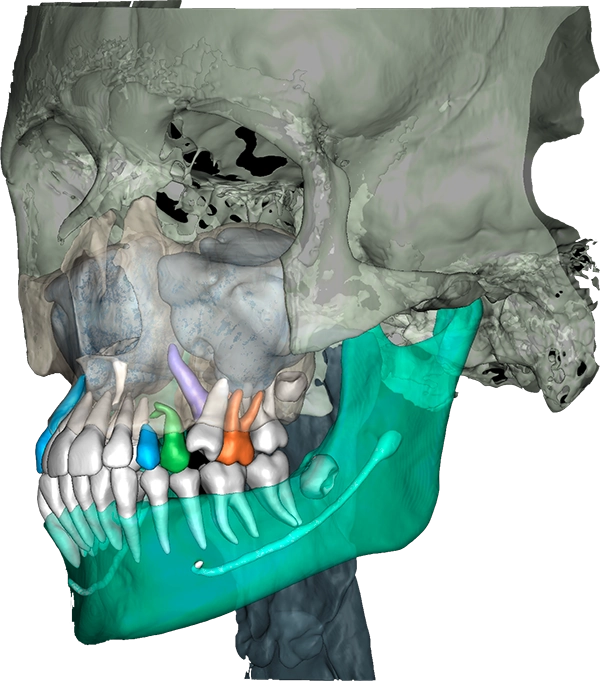

- Инвиво — расчёт 3D-цефалометрии, оценка КТ

5. Работа в 3D

- ручная сшивка сканов с КТ;

- автоматическая сшивка сканов с КТ для печати моделей;

- Отличие 3D-цефалометрии от 2D. Принципы построения точек через ИИ (на основе обучения нейросети);

- Оценка нарезки зубов (в т.ч. анализ корональных срезов для оценки дистализации);

- Оценка суставов на КТ (какие срезы смотреть, как оценивать);

- Анализ симметрии (прямая цефалометрия);

- Penn-анализ для оценки трансверзальных несоответствий;

- Анализ дыхательных путей;

Важность трехмерной визуализации клинической ситуации:

- визуализация для врача при ретенции зубов. Планирование механики лечения;

- оценка положения ВНЧС;

- возможность анализа прогресса лечения в различных клинических ситуациях;

- инструмент для общения с пациентом на различных этапах лечения;

- выгрузка STL-файлов после сегментации;

Использование рентгенологического отчета при планировании лечения (компромиссные зубы, решение об удалении зубов)